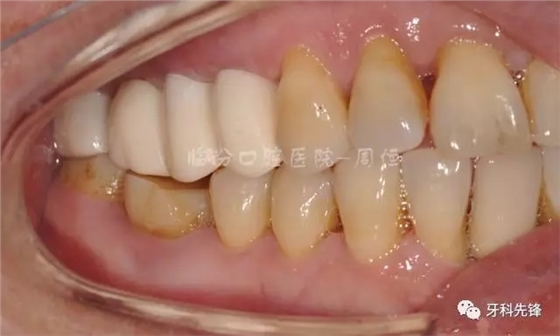

圖2 術(shù)前側(cè)位咬頜照

圖5拆除原修復(fù)體側(cè)位咬合照